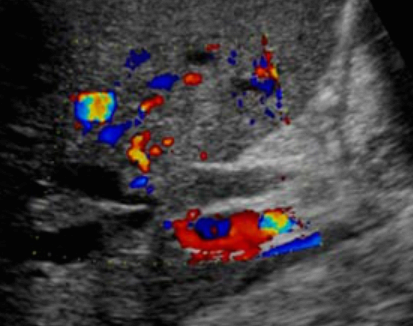

미리찌 증후군 (Mirizzi's syndrom) Mirizzi's syndrom 은 담낭경부, Hartmann's pouch 혹은 담낭관의 결석에 의해 총 간관(CHD)이 폐쇄되는 질환이다. 총 간관(CHD)이 협착되면서 상부담관은 확장되고 하부담관의 직경은 정상으로 나타난다. 증상은 폐쇄성 황달, 복부통증, 발열 등이 나타난다. 급성담낭염이 있으면서 담관폐쇄를 동반할 경우 의심해 볼 수 있다. 담낭절제술 후에 남아있는 담낭관의 결석이 총 간관(CHD)을 직접 누르거나 염증성 협착을 유발하기도 한다.

US finding

- 담낭관 또는 담낭 경부에 결석이 확인된다.

- 총간관(CHD) 또는 담낭관(cystic duct)의 확장소견이 보인다.

- 간내외 담관의 확장이 관찰된다.